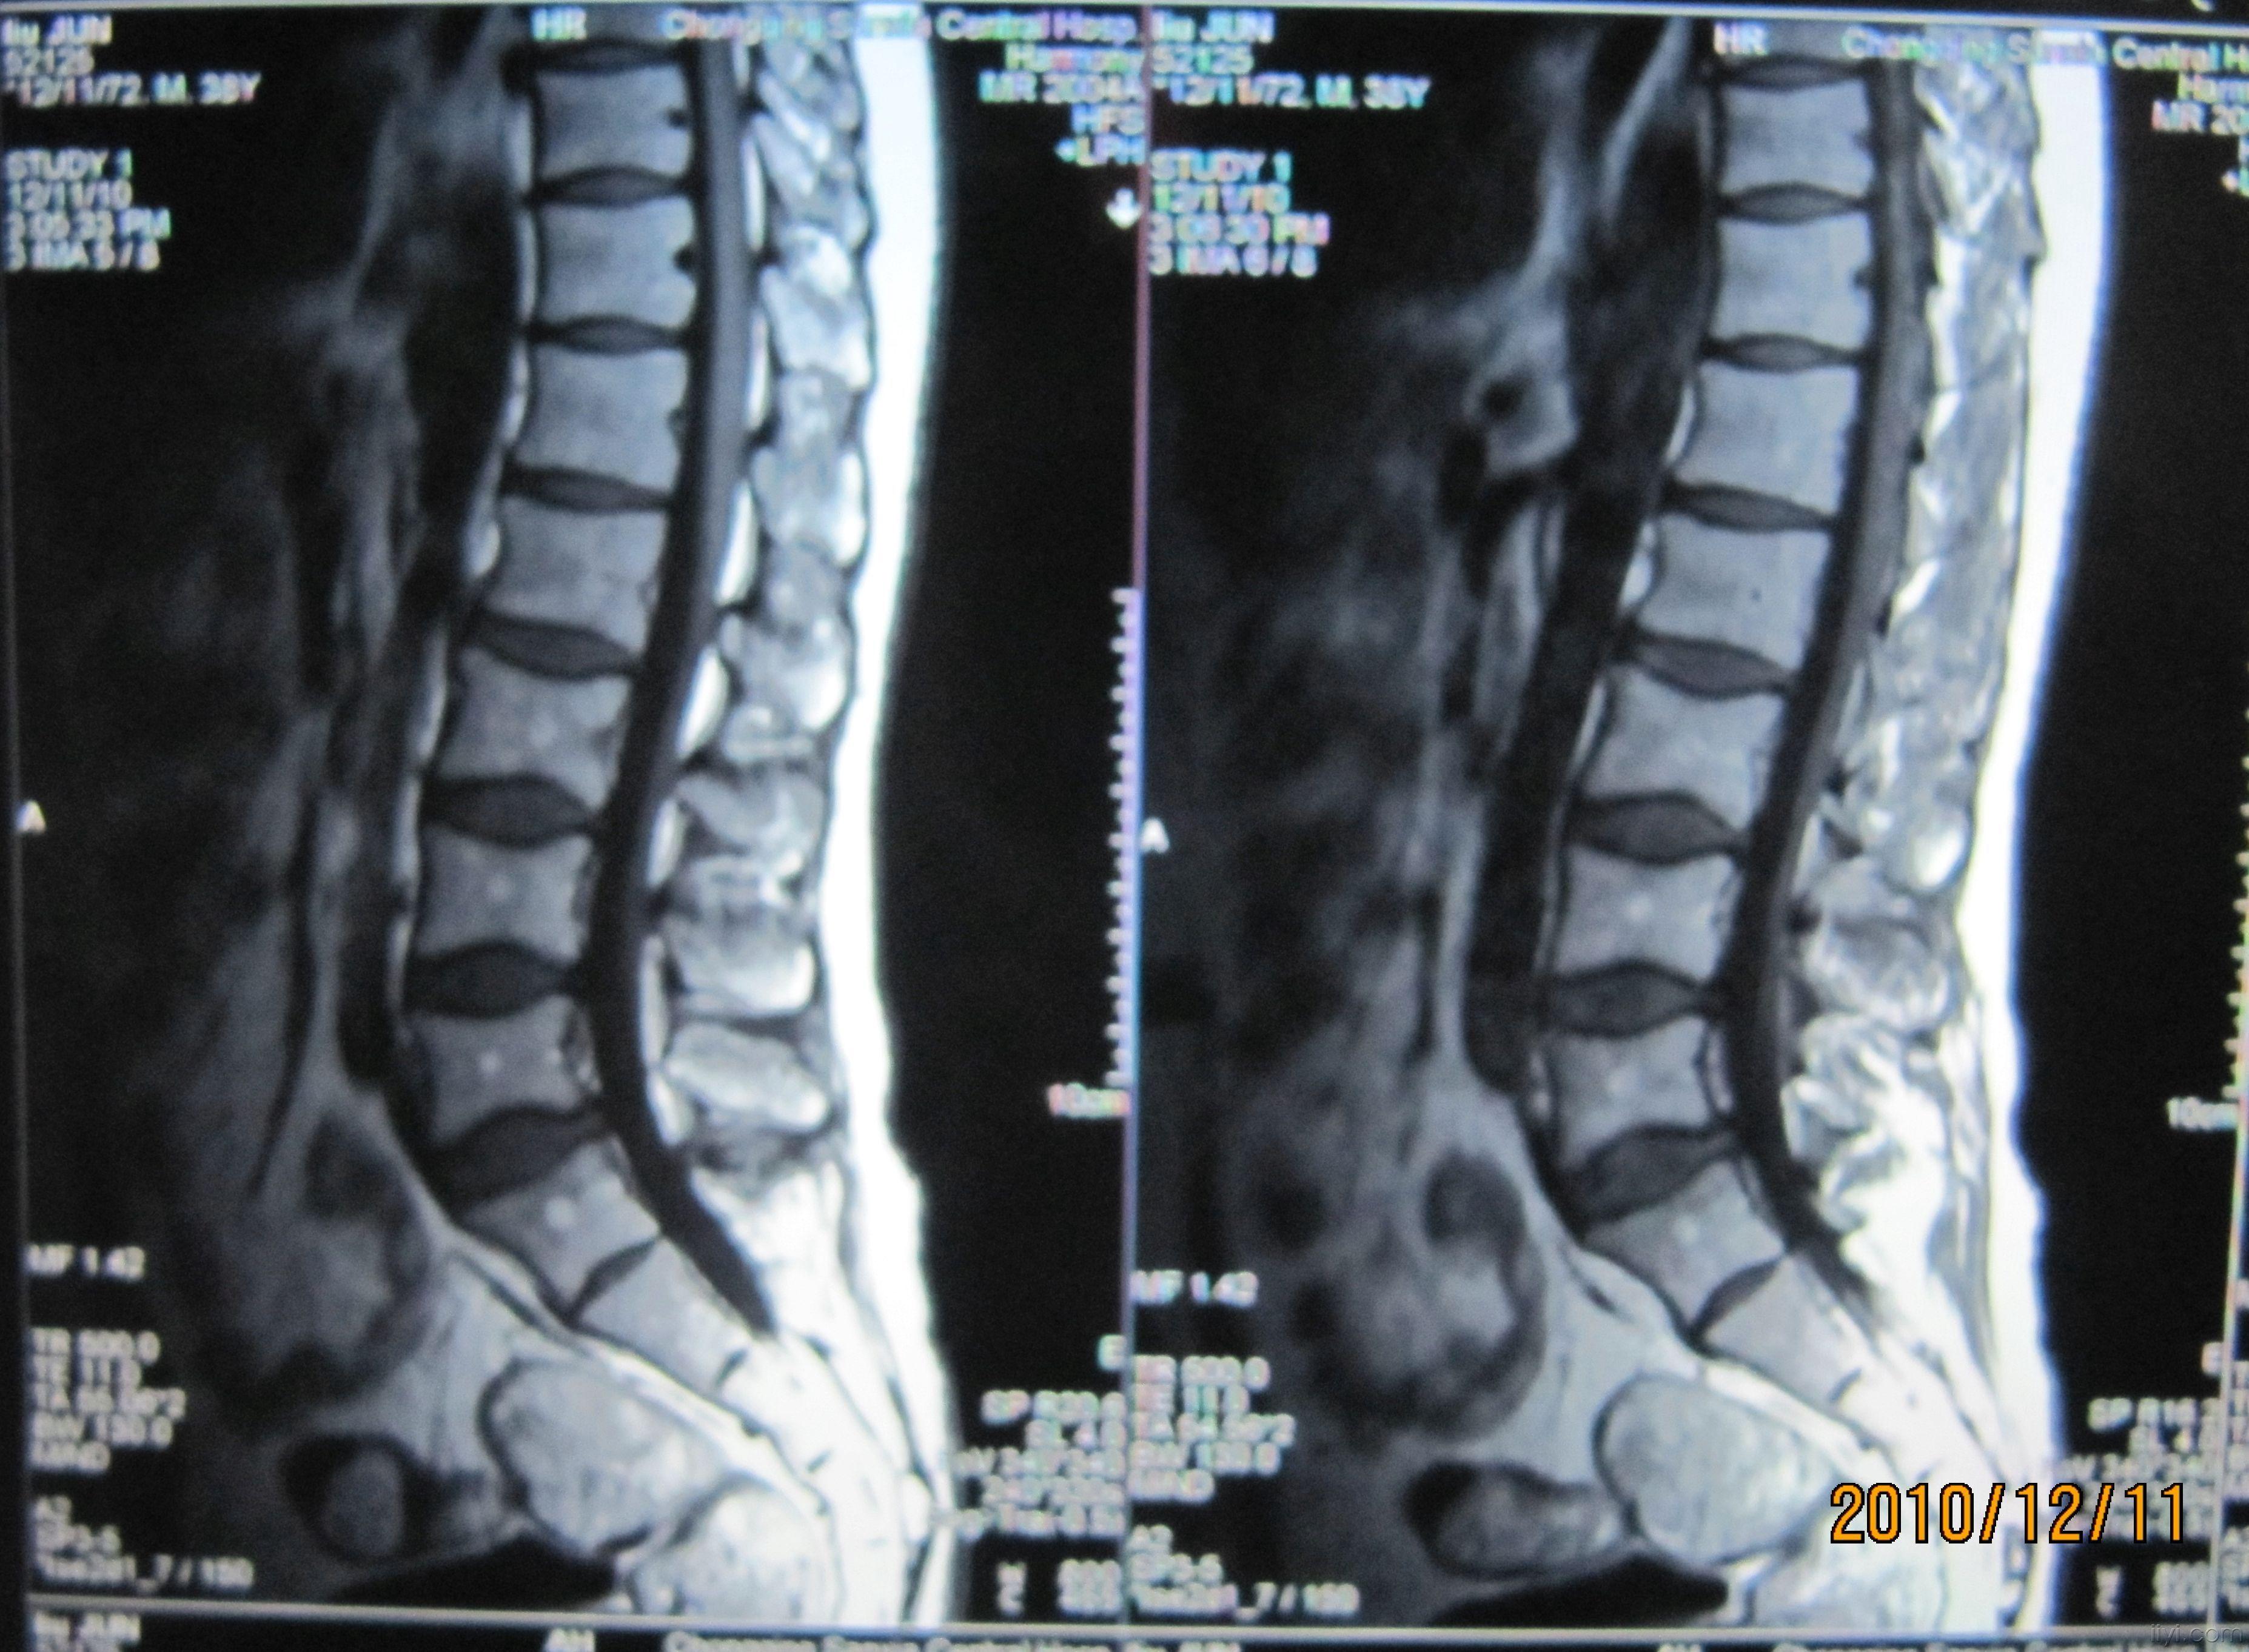

核磁共振腰椎检查图片

核磁共振腰椎检查图片,核磁共振检查图片

郭先生术前腰椎核磁共振片子.

患者术前核磁共振片:腰5/骶1间盘突出.

磁共振显示腰4/5椎间盘脱垂